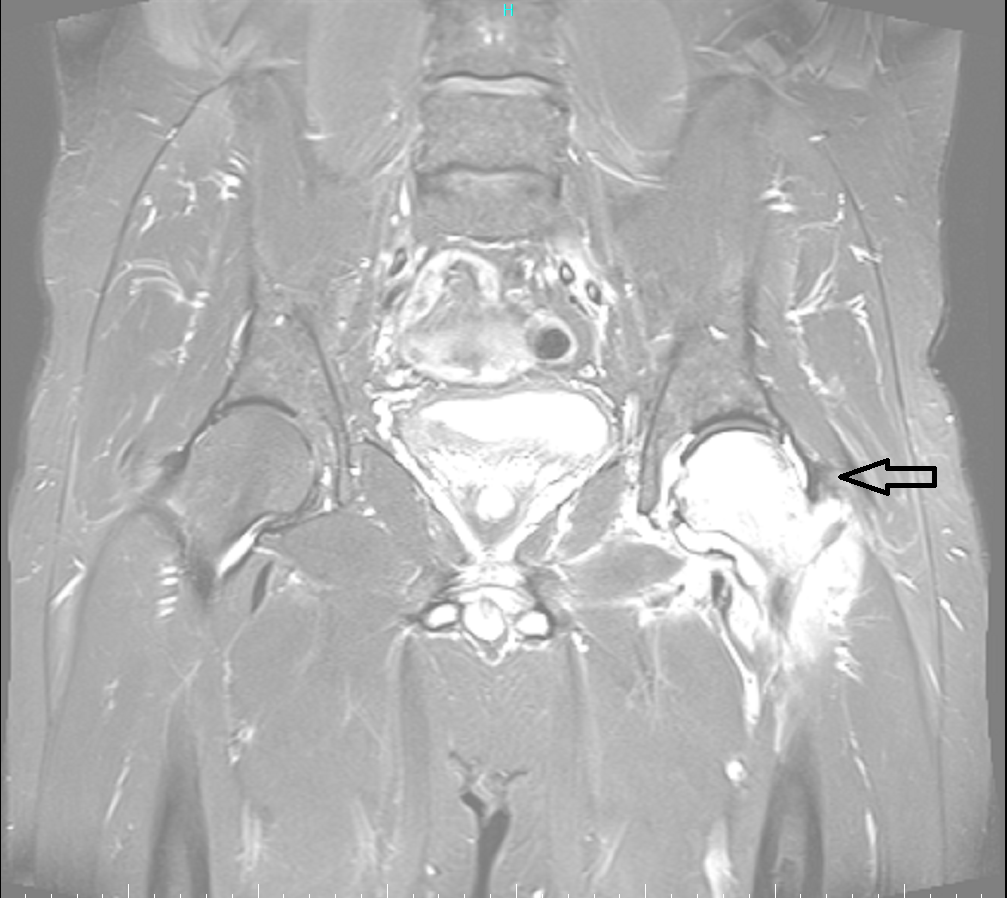

Ασθενής με οστικό οίδημα αριστερού ισχίου

Ασθενής 51 ετών, με αιφνίδιο άλγος από μηνός συνεχώς επειδυνούμενο. Η μαγνητική τομογραφία έδειξε ότι υπάρχει εκτεταμένο οστικό οίδημα αριστερού ισχίου (βέλος). Πραγματοποιήθηκε έγχυση ισχίου με υαλουρονικό και παυσίπονα. Ο ασθενής ένιωσε άμεσα ανακούφιση με πλήρη υποχώρηση των συμπτωμάτων που διατηρείται έως σήμερα 1.5 χρόνο μετά.